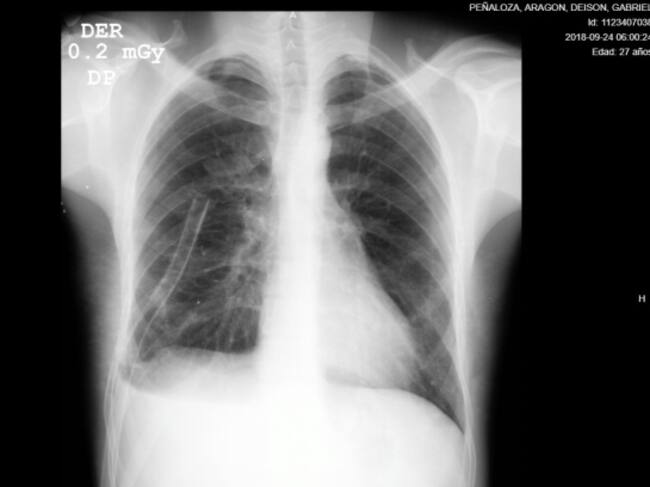

Al borde de la muerte estuvo Deyson Peñaloza, luego de una herida con arma cortopunzante que estuvo a centímetro y medio de perforar el corazón. El joven fue llevado al área de urgencias de la Unidad de Servicios de Salud (USS) Meissen, allí logró sobrevivir.

Mientras el paciente era atendido en el servicio de urgencias, en la unidad transfusional de la Subred Sur se le realizaron pruebas de laboratorio para reservar sus hemoderivados y así poder adelantar el procedimiento quirúrgico, dada la condición crítica en la que fue recibido.

“El paciente ingresó inconsciente y con 98 % de probabilidades de morir, pero luego de la inmediata atención y valoración que recibió el joven, tras salir del área de reanimación, fue llevado a sala de cirugía donde se intervino de manera exitosa”, comentó Josef Kling, médico especialista de cirugía general de la Subred Sur.